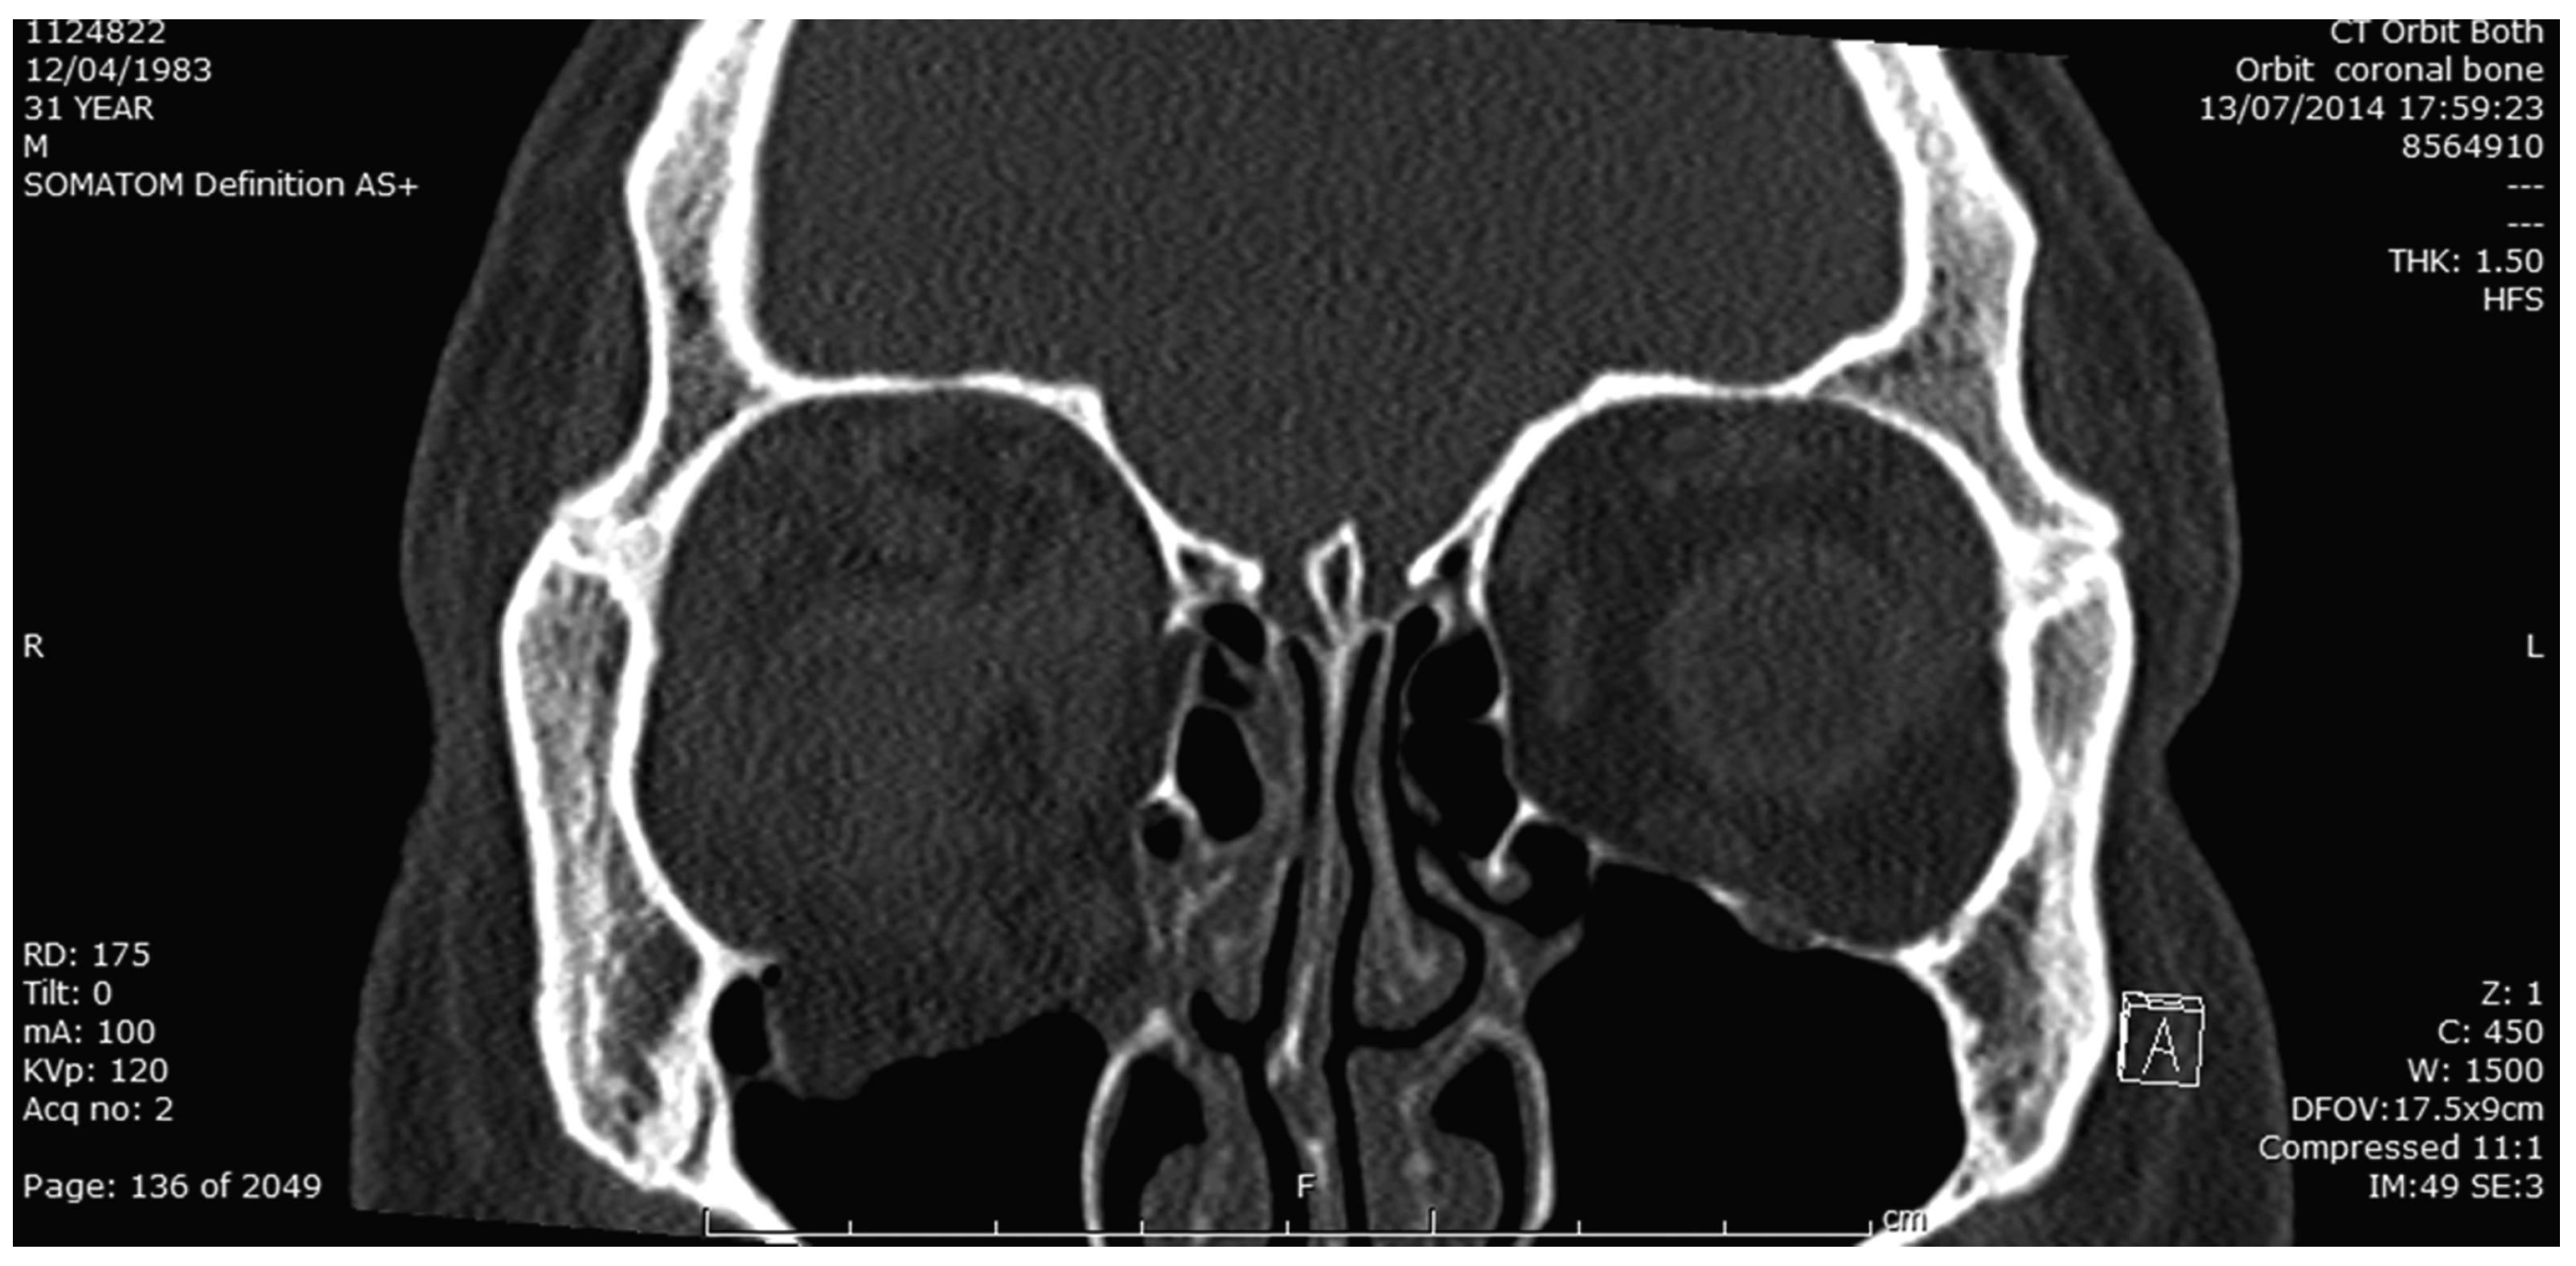

The postprocedure intraocular pressure was 23 to 29 mm Hg and there was a palpable reduction in orbital tension. Subsequent orbital imaging (Figure 1, Figure 2 and Figure 3) confirmed a displaced/punched-out fracture of the orbital floor (unhinged, type III) [1] with fracture of the medial wall, hematoma in the orbital compartment. The globe was entrapped between the orbital rim inferiorly, hematoma posterosuperiorly, and edematous preseptal tissue anteriorly. There was no orbital foreign body.

Figure 3. Coronal bone window CT image showing floor and medial wall fracture of R orbit.